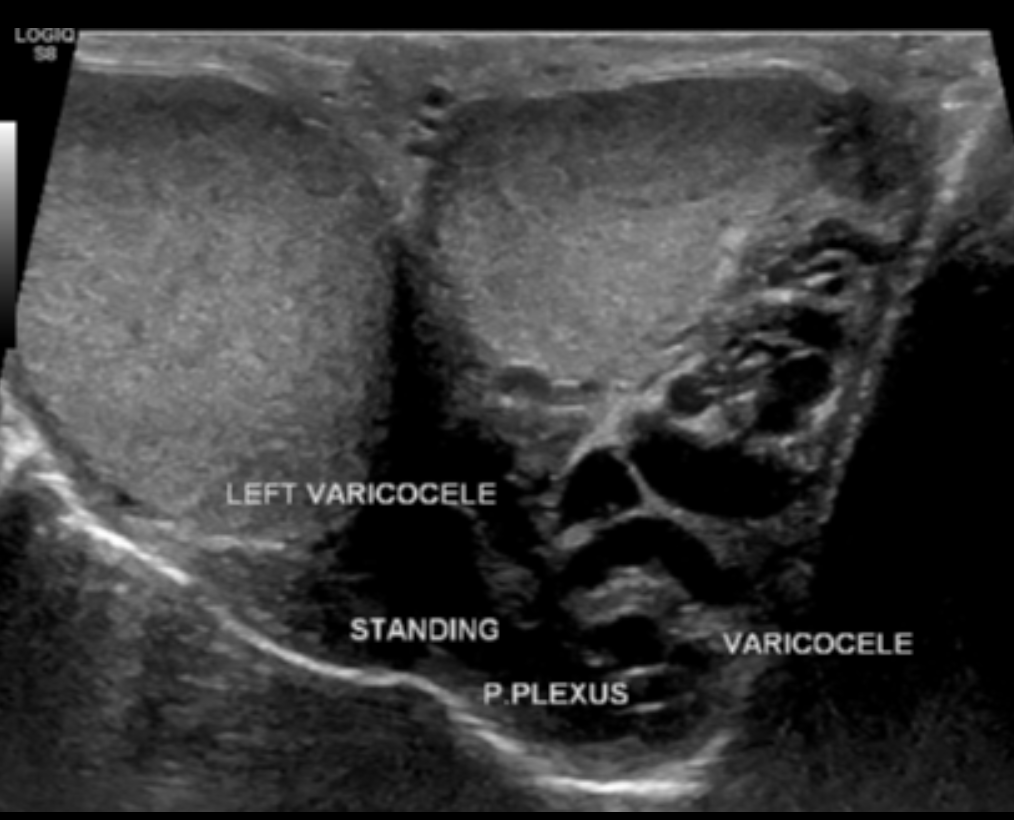

Varicocele

• Dilated vessels outside of testicle

• Should have some doppler flow

• If suspect this, have patient valsalva while ultrasounding and should see increased flow within the vessels